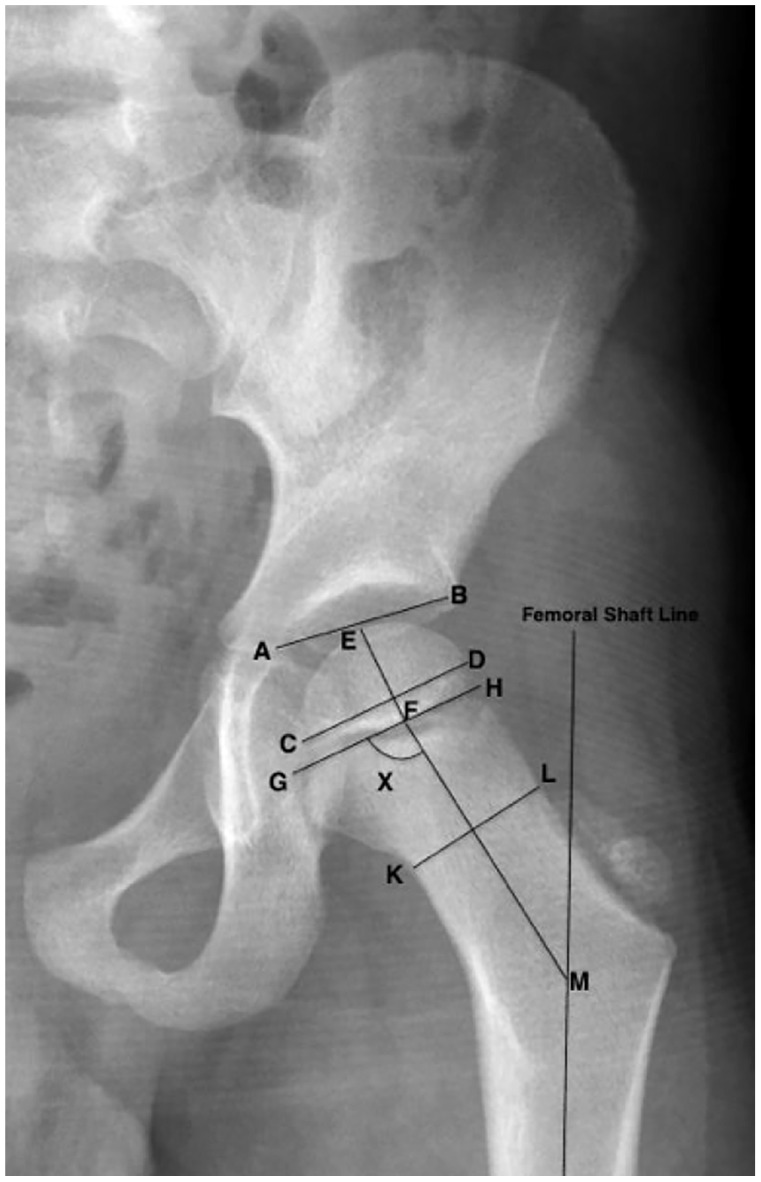

Methods: Children with cerebral palsy and spinal muscular atrophy were compared with typically developing children aged 6 months to 11 years. Routine pelvic radiographs were evaluated using measures of hip geometry for the proximal femur and acetabulum. The data were analyzed using general linear models to estimate the developmental patterns according to age and diagnosis.

Results: One hundred eighty-four children met the inclusion criteria: 58 spastic cerebral palsy Gross Motor Function Classification System I-V (263 hips), 32 spinal muscular atrophy (79 hips)), and 94 typically developing (187 hips) were included with a mean age of 4.9 ± 3.1 years. Using spinal muscular atrophy as a reference, significant differences in proximal femoral development included long thin versus short neck (p < 0.01) and round versus flat epiphysis (p = 0.001). A thin neck-wide epiphysis was found in spinal muscular atrophy versus thick neck-small epiphysis for typically developing (p < 0.05). The ratio of acetabular width to proximal femoral epiphysis width differed significantly for typically developing (p = 0.001) compared with cerebral palsy and spinal muscular atrophy. There was a negative correlation between migration percentage and acetabular width to epiphysis width in children with cerebral palsy, but no correlation in children with spinal muscular atrophy.

Conclusion: Hip geometry was impacted by the force environment experienced during growth. These findings emphasize the crucial roles of gross motor function, muscle tone, and strength differences in determining hip morphology.